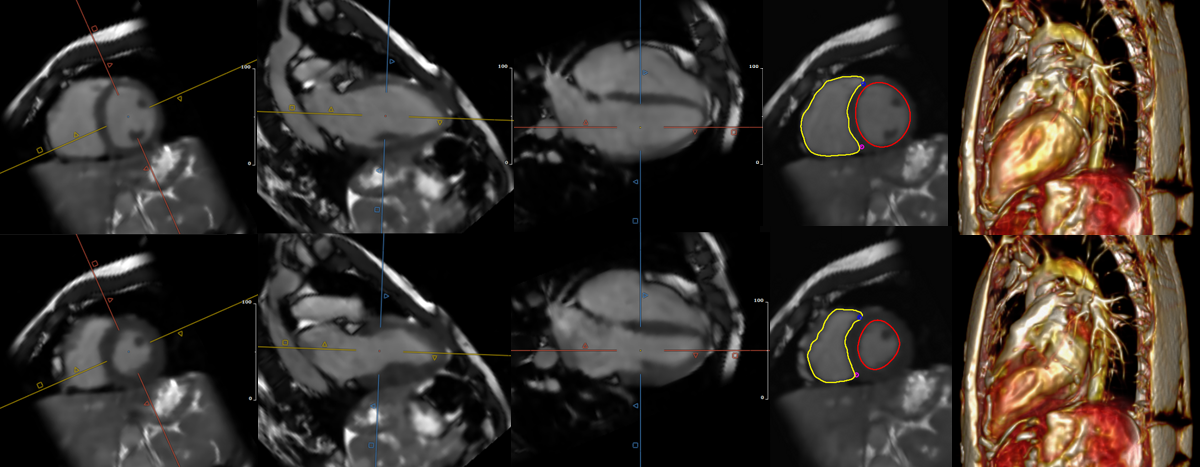

Diastolic short axis frames for a CHD patient with difficulty holding their breath. While the 15s 1-BH scan at 2.5mm was diagnostic (a), a 3-BH scan was added at 1.7mm isotropic resolution and 12s per BH (b-d). Images (c) and (d) show the 3-BH images in short axis and 4-chamber views with inter-BH motion compensation, and (b) shows the artifacts arising if the latter is omitted during reconstruction.